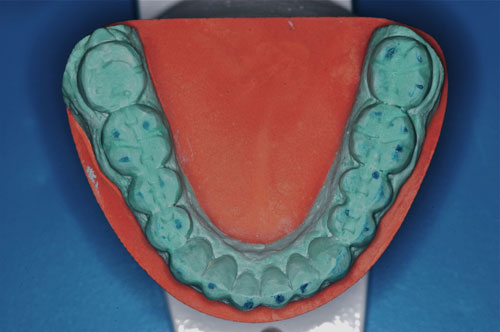

ESTUDIO ESTÁTICO DE LOS MODELOS PREVIOS A LA PRIMERA REHABILITACIÓN APORTADOS POR LA ENFERMA:Modelos Color Blanco

B- ESTUDIO ESTÁTICO DE LOS MODELOS PREVIOS A LA 1ª REHABILITACIÓN APORTADOS POR LA ENFERMA: (La situación oclusal que la enferma tenía antes de que la tocara un dentista (MODELOS COLOR BLANCO)

ESTUDIO ESTÁTICO Y CINEMÁTICO DE LA OCLUSIÓN PRESENTE: Modelos Color Verde

Se realiza un montaje en articulador semi ajustable, mediante la técnica de arco facial convencional para el maxilar superior, y mediante relajación con Laminillas de Long para el inferior. No satisfechos de la certeza del primer montaje, construimos en el un Jig de Lucia que dejamos toda una noche en boca para remontar el inferior al día siguiente a primera hora.